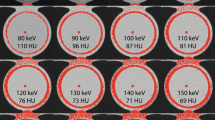

First, the dynamic phantom was scanned on a dual-source PCCT (NAEOTOM Alpha, Siemens Healthineers) with the routinely used clinical reference protocol: tube potential 120 kV; axial scan technique; automatic tube current modulation (ATCM) with image quality level 16 (CareIQ, Siemens Healthineers), reconstruction technique filtered-back-projection (FBP or QIR off); field-of-view 220 mm; matrix 512 × 512; slice thickness/increment at 3/1.5 mm; reconstruction kernel Qr36. Second, additional acquisitions were performed for both phantom sizes at 70, 90, Sn100, Sn140, and 140 kV, at the same image quality level of 16 using ATCM that aims at keeping image noise constant while changing kV. All scans were reconstructed at a VMI level of 70 keV. Each acquisition was repeated five times, with manual repositioning of the setup between each scan (2 mm translation, 2° rotation), to introduce inter-scan variability.

The effective tube current time products, based on the ATCM level 16, are indicated in Table 1. Reference volumetric CT dose index (CTDIvol) values, retrieved from the radiation dose structured report, at 120 kV, were 2.06 and 2.78 mGy for the medium and large phantom sizes, respectively. For the medium phantom, the largest decrease in radiation dose with respect to the reference at 120 kV was achieved for Sn100-kV acquisitions, at 22% (Fig. 2). Acquisitions at 90 kV also reduced the radiation dose, while all other tube potentials increased radiation dose for medium-sized patients. For the large phantom, Sn100- and Sn140-kV acquisitions resulted in a decrease in radiation doses of 19% and 3%, respectively.